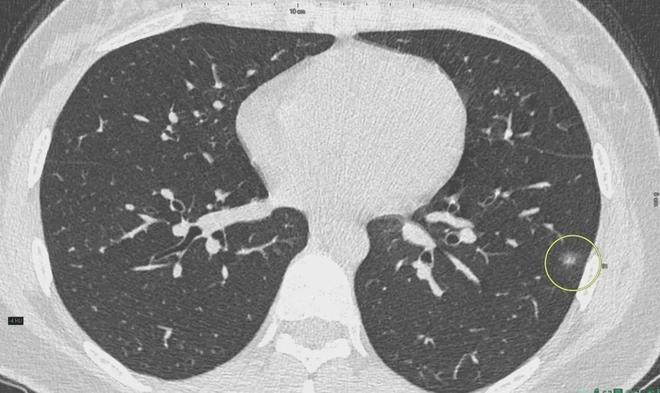

6、定期體檢:定期進(jìn)行肺部檢查,及時(shí)發(fā)現(xiàn)并治療肺結(jié)節(jié)。

對于已經(jīng)發(fā)現(xiàn)肺結(jié)節(jié)的患者,應(yīng)及時(shí)就醫(yī),進(jìn)行進(jìn)一步的檢查和治療,醫(yī)生會(huì)根據(jù)患者的具體情況制定個(gè)性化的治療方案,包括藥物治療、手術(shù)治療等,早期發(fā)現(xiàn)、早期治療是提高肺結(jié)節(jié)治愈率的關(guān)鍵。